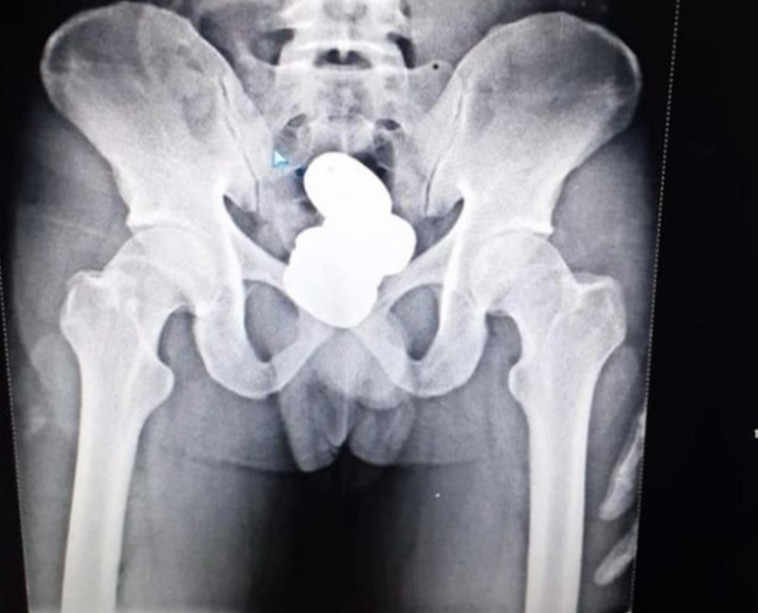

תנועה אחת חשודה חשפה הברחה של כמעט קילו זהב, שהוחבא בצורת ביצים בתוך הבטן של המבריח. מוחמד שריף נתפס בשדה התעופה אימפריאל שבהודו כשהיה בדרכו לניו דלהי, אחרי שעורר את חשדנותו של אחד הבודקים בשדה. כשמהחיפוש החיצוני לא עלה דבר, אחד מאנשי הצוות התעקש לבדוק את גופו גם בבדיקת רנטגן, שחשפה את התחבולה.

מטילי הזהב בבטנו של המבריח

מטילי הזהב בבטנו של המבריח | צילום: Imphal Airport

על פי הדיווחים באתר החדשות The Indian Times, הגורמים הרשמיים בשדה התעופה גילו כי שריף החביא בתוך הבטן שלו למעלה מ-900 גרם של מטילי זהב, שנכנסו לגופו דרך פי הטבעת. לאחר הוצאת ביצי הזהב מגופו של המבריח, הזהב נשקל ושווי הוערך בכ-42 אלף רופי (כ-190 אלף שקלים). שריף נעצר בתום האירוע ונלקח לחקירה אצל המשטרה המקומית כדי להבין האם בחר להבריח את הזהב בעצמו או שמא העביר מידיים אחרות.